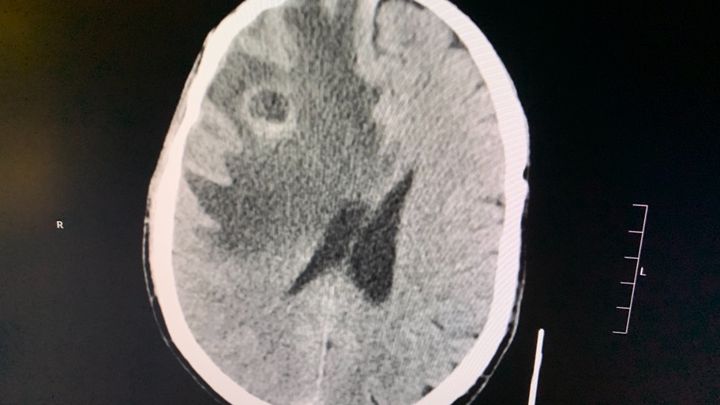

Her physical pain was mirrored by her depression and deep post-traumatic stress. Yet she continued the work she loves most until back problems recently forced her to resign also from 911 . Because of 911 she differs from PTS , fibromyalgia Disk generation degeneration disease and now can and and numerous tumors in the brain cancer and throughout her body .

Beginning this past July 4 weekend, while considering her next steps, Mo began suffering severe headaches and had multiple bad falls over the next several weeks, finally sending her to the ER. A brain tumor was found, and Mo was rushed to Maryland University Hospital for emergency surgery.

A lung tumor was also found. Like far too many other 9/11 heroes who worked on the front-lines, Mo has been thrown into a fight for which she never asked for , and which no one deserves.

Doctors are evaluating various protocols that will best battle these multiple tumors, and lesions . She will begin immuno-suppressive and or Chemo treatment once all biopsies are compleat - Mo is due to start the second such treatment shortly.

Her physical pain was mirrored by her depression and deep post-traumatic stress. Yet she continued the work she loves most until back problems recently forced her to resign also from 911 . Because of 911 she differs from PTS , fibromyalgia Disk generation degeneration disease and now can and and numerous tumors in the brain cancer and throughout her body .

Beginning this past July 4 weekend, while considering her next steps, Mo began suffering severe headaches and had multiple bad falls over the next several weeks, finally sending her to the ER. A brain tumor was found, and Mo was rushed to Maryland University Hospital for emergency surgery.

A lung tumor was also found. Like far too many other 9/11 heroes who worked on the front-lines, Mo has been thrown into a fight for which she never asked for , and which no one deserves.

Doctors are evaluating various protocols that will best battle these multiple tumors, and lesions . She will begin immuno-suppressive and or Chemo treatment once all biopsies are compleat - Mo is due to start the second such treatment shortly.